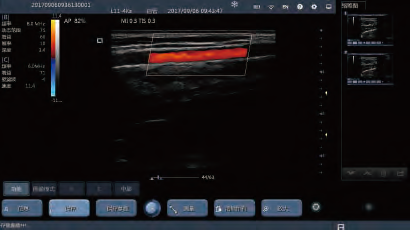

Display mode : B, B&M, 2B, 4B, THI, Color, Power, PW

Convex Linear Color Doppler Probe Wireless Ultrasound Probe with Scanning Depth 310mm

| Modes | B, M, 2B, 4B, THI, Color, Power, PW (only color Doppler version have Color, Power, PW) |

| Digital Technology | Wide-angle imaging Panoramic focusing technology Frequency compounding Space compounding Rolling M technology Real-time Dynamic Aperture Tissue Harmonic Imaging Tissue Specific Imaging |

Convex Linear Color Doppler Probe Handheld Ultrasound Scanner With Scanning Depth 310mm Images |